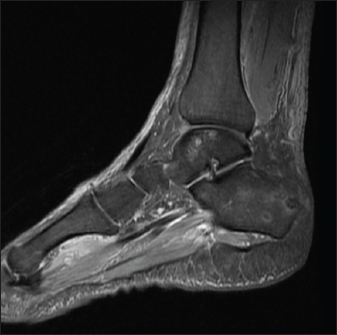

57-year-old male with diabetes, presented with complaints of intermittent fever for 4 weeks. It was associated with loss of appetite and significant loss of weight. No associated pain abdomen, vomiting, altered bowel and bladder habits. On physical examination, he had hepatomegaly. Workup for pyrexia of unknown origin was done. Mantoux test was negative. Chest X-ray showed prominent Broncho vascular markings. Contrast CT of abdomen showed splenic infarct with intraluminal short segment partial thrombosis of the proximal splenic vein along with heterogeneously enhancing subcarinal and right lower paratracheal mediastinal lymph nodes with central necrosis — probably granulomatous infection. Endobronchial ultrasound guided fine needle aspiration biopsy of mediastinal lymph nodes was done. Cytology was negative for malignancy. Histopathological report was suggestive of acute suppurative inflammation, with negative gram stain and Acid-Fast stains. But his blood culture grew B. pseudomallei and the whole clinical picture was suggestive of melioidosis. He also developed pain and swelling around left ankle joint while in hospital. On examination he had tenderness and warmth around left ankle with restricted movements. Orthopaedics consultation was obtained and an MRI ankle joint (Fig. 3) was done which showed features of acute osteomyelitis of calcaneum (multiple micro abscess) with adjacent intermuscular and fascial abscesses. Ultrasound guided aspiration of the plantar abscess was done and pus was aspirated. Culture grew B. Pseudomallei. The patient was diagnosed with osteomyelitis caused by melioidosis and was treated with intravenous Meropenem for 6 weeks, followed by oral cotrimoxazole for another six months. The patient had a good recovery and was followed up in the outpatient clinic.

Fig. 3. MRI Rt. foot—patient 2.